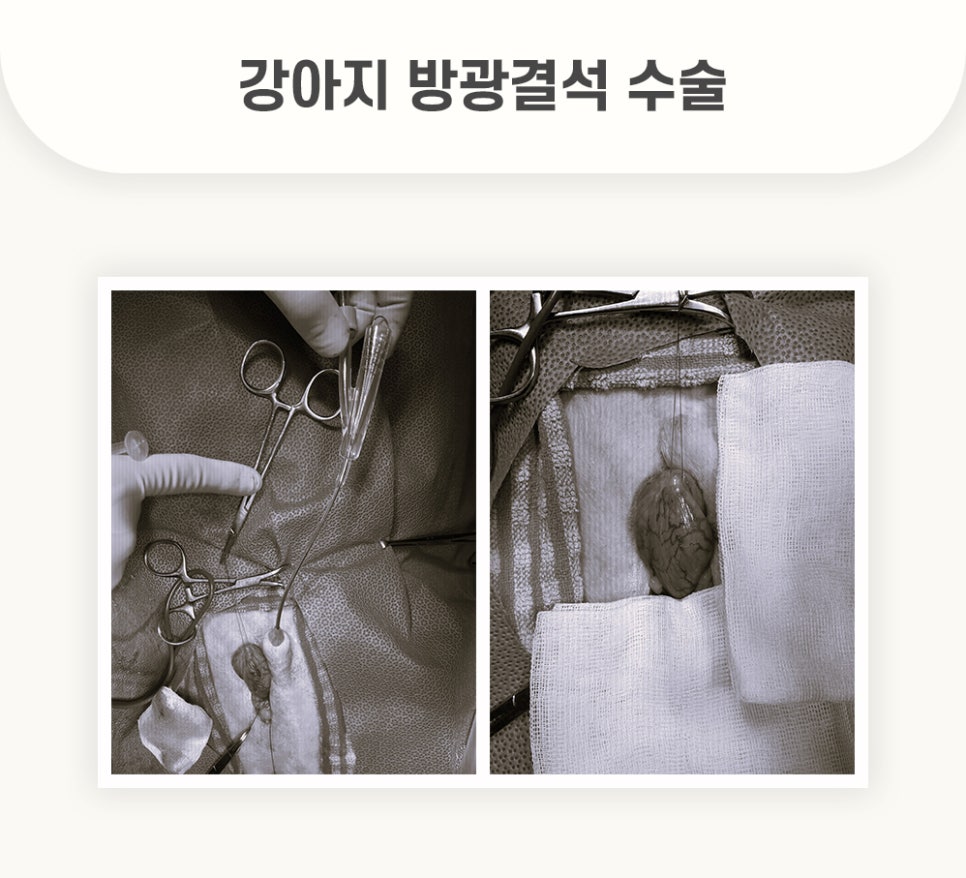

[수술 중]

복** 환자의 수술은 경기동물의료원 의료진의 집도하에 순조롭게 진행 되었습니다.

개복 후 방광을 절개하여 결석을 모두 제거하는데 성공하였습니다. 또한 경기동물의료원 의료진의 면밀한 봉합으로 수술을 마무리 하였습니다.